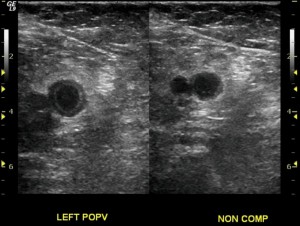

How To Case Study: Deep Vein Thrombosis Detection With ...

Visit http://www.sonosite.com/education for more videos like this. Learn about how to detect deep vein thrombosis using portable ultrasound from Dr Perera in this first part of a 2 part series. Visit http://www.sonosite.com/education for more videos like this. ... View Video

Venous US Of Lower-Extremity Deep Venous Thrombosis: When Is ...

Venous US of Lower-Extremity Deep Venous Thrombosis: When Is US Insufficient?1 Damian E. Dupuy, MD low-up of prior DVT. In this setting, US images of a lower-extremity vein can be equivocal. At this point, one could elect to repeat US in 3 days racy of color Doppler ultrasound in the ... Retrieve Doc

Venous Duplex Ultrasound Of The Lower Extremity In The ...

Venous Duplex Ultrasound of the Lower Extremity in the Diagnosis of Deep Venous Thrombosis 23 Bruce L. Mintz and Robert W. Hobson 11 Introduction Venous Duplex Ultrasound in the Diagnosis of DVT 325 Ag.23.3. ... Read Here